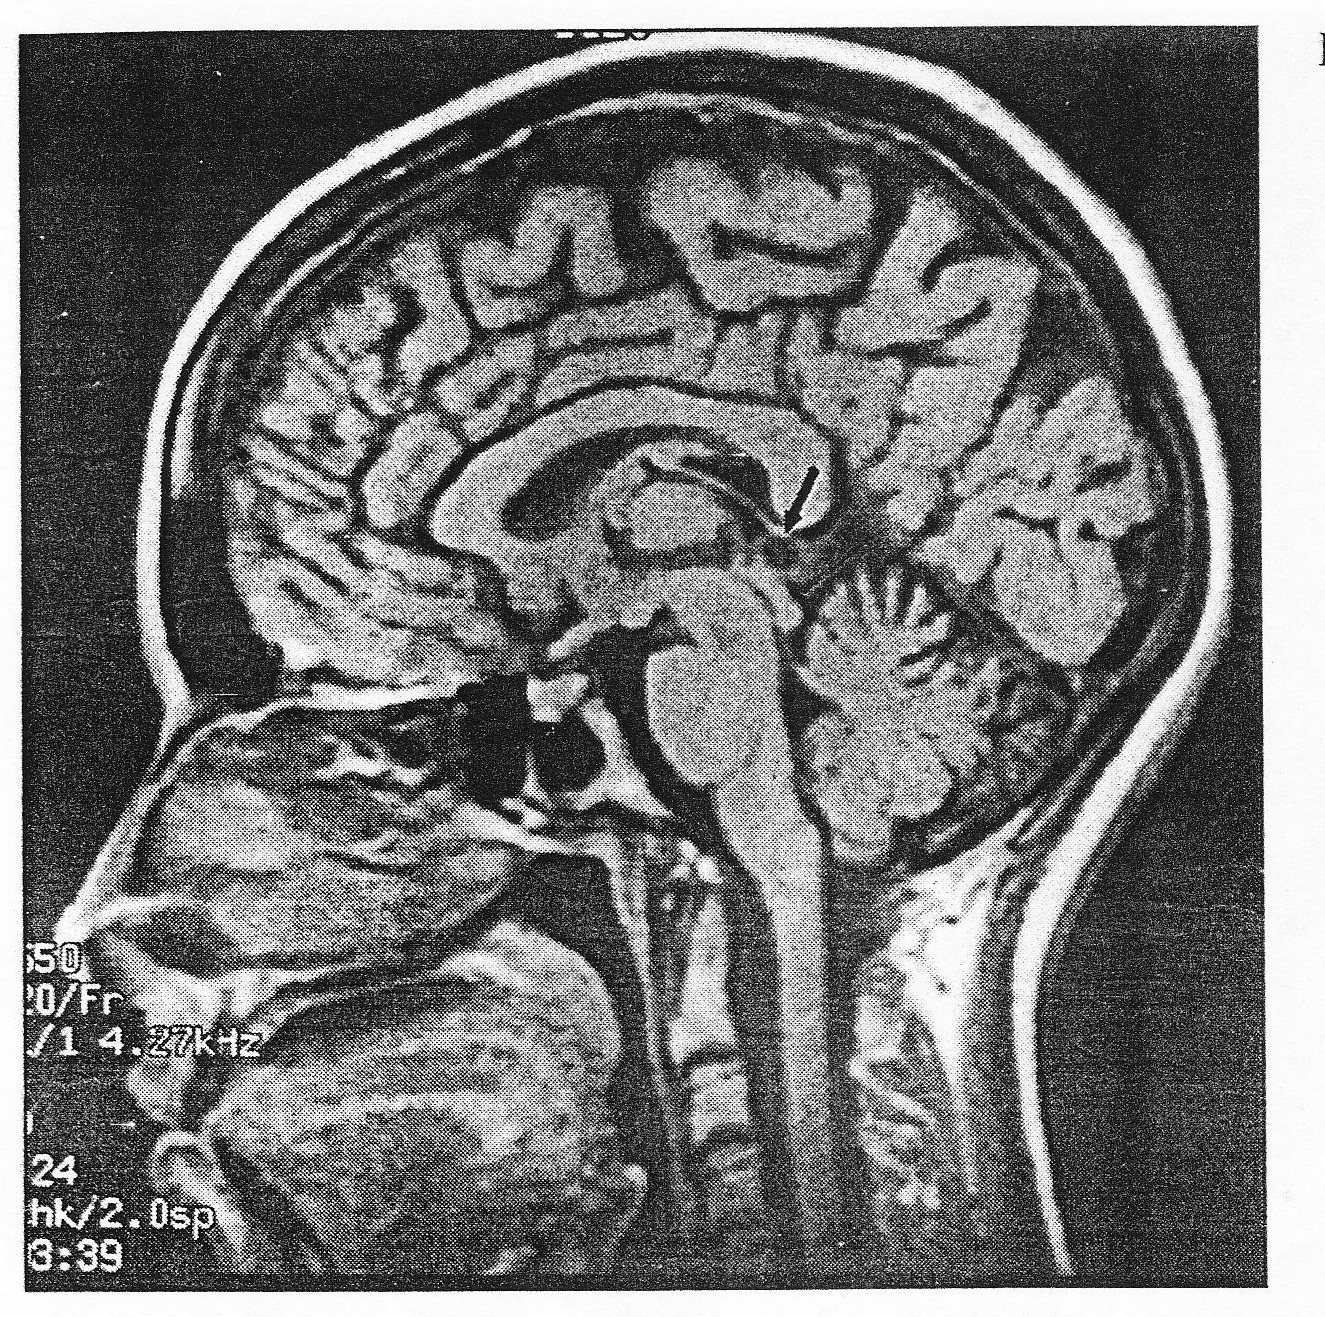

A 30-year-old female experienced an episode of left visual field scintillating scotoma followed by a left homonymous visual field defect. Aproximatelly 30 minutes later, a severe throbbing right hemicranial headache began and lasted for the reminder of the day. The patient was later investigated with an MRI. A pinealcyst was identified (Figure 35)

A. males > 50 years of age

B. female >50 years of

C. Females 20-40 years of age

D. males 20-40 years of age

C. Females 20 - 40 years